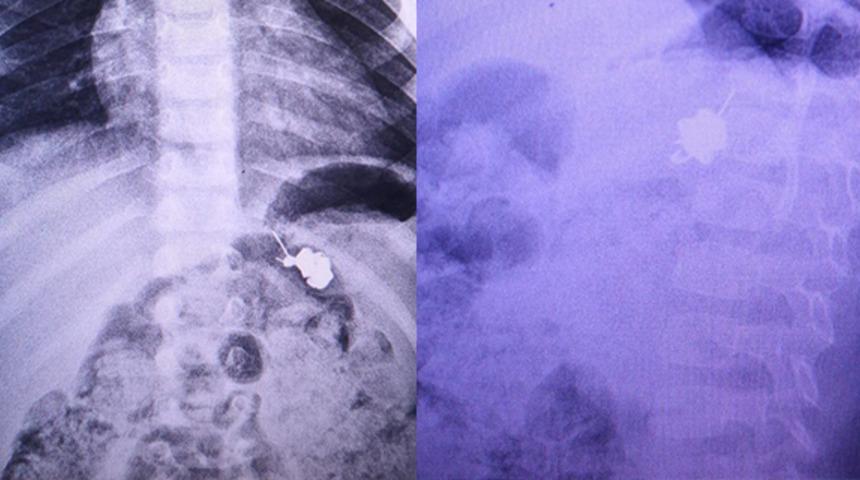

Yasin Yıldırım, çengelli iğnenin bağırsağında takılı kalmasının tespit edilmesiyle cerrahi müdahale için Dörtçelik Çocuk Hastanesi'ne sevk edildi. Burada yapılan operasyonla küçük çocuğunun bağırsağına takılan çengelli iğne çıkarıldı. Yasin Yıldırım'ın sağlık durumunun iyi olduğu öğrenildi.